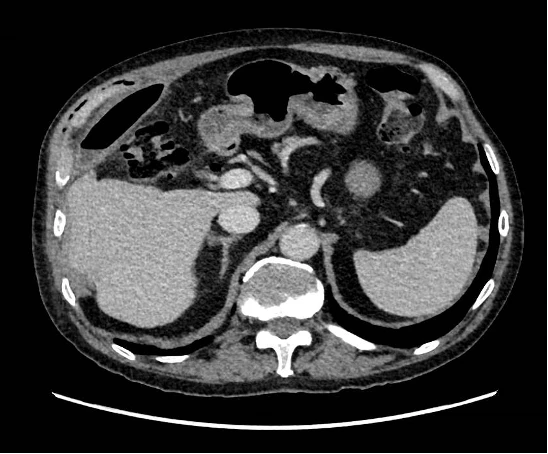

Un patient de 69 ans, connu pour maladie des anticorps anti-phospholipides et une fibrillation auriculaire anticoagulée, présente des douleurs de l’hypochondre D depuis 2 semaines, péjorées le matin et après les repas. Le patient a chuté il y a quelques mois. Au status le patient est stable, afébrile, et présente des douleurs insupportables à la palpation basi-thoracique D. L’hypochondre D est également douloureux. On retrouve de l’emphysème sous-cutané basithoracique D. Le laboratoire met en évidence : leucocyte à 34 G/​l, à prédominance neutrophilique, une élévation de la CRP200 mg/​l, des tests hépato-pancréatiques dans la norme.

Bilan radiologique complémentaire :

Le bilan radiologique suivant peut correspondre à :